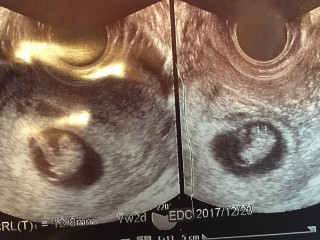

二卵性の双子です。先週心拍が確認できましたが、その時はただの丸だったのに、今は長くなって2つとも1.3㎜ほど。もうすぐ胎芽から胎児に。まだまだ不安は尽きないけれど、成長が楽しみです。

一週間まえ8mmと言われ今日は12.8mm!見事にすくすく育ってくれてる(^.^)